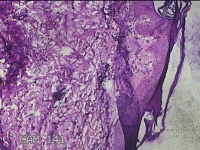

右侧腰臀部包块

性别

女

年龄

44岁

临床诊断

臀部良性肿瘤

一般病史

发现右侧腰臀部包块1个月余。

标本名称

大体所见

灰白粉红色包块0.8x0.3x0.2cm一个,表面光滑。

图1

良性病变。